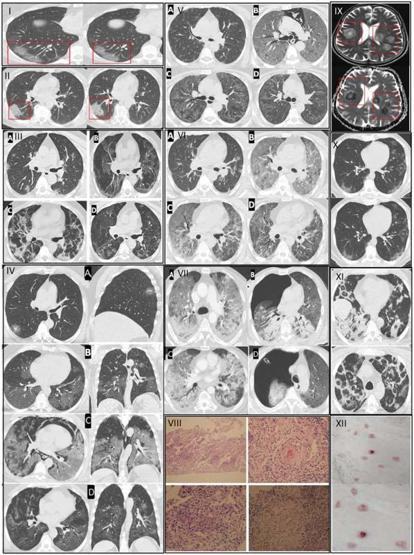

Kovid-19 sonrası genç yaşta ani ölüm vakaları arttı. Bunun nedeninin Kovid-19 virüsünün damarlarda oluşturduğu kalıcı hasar olduğunu belirtiliyor. Kovid-19 aşılarının bu durumu etkilemediğini söyleyen uzmanlar önemli uyarılarda bulunuyor.

Göğüs Hastalıkları Uzmanı Prof. Dr. Şevket Özkaya, pandemi sonrası genç yaşta ani ölüm vakalarında artış gözlendiğini belirterek bunun nedeninin Kovid-19 virüsünün damarlarda oluşturduğu kalıcı hasar olduğunu ifade etti. Prof. Dr. Özkaya, son dönemde spor sırasında veya sonrasında yaşanan beklenmedik kalp krizlerinin, virüsün damar yapısı üzerindeki etkilerinden kaynaklandığını söyledi.

Prof. Dr. Özkaya, Kovid-19'un özellikle kılcal damar düzeyinde ciddi hasar bıraktığını belirterek, "Pandemi boyunca takip ettiğimiz binlerce hastada ‘endotelit’ dediğimiz damar iç yüzeyi hasarının ani ölümleri tetiklediğini saptadık ve uluslararası dergilerde yayınladık. Avrupa Kalp Dergisi’nin son verilerinde de bu durum ‘Kovid-19 sonrası damar yaşlanmasının hızlanması’ olarak tanımlanmıştır.

Virüsü geçirenlerde damar yaşı, takvim yaşından daha yaşlı hale geliyor. Bu etki bazı kişilerde 5 yıllık yaşlanmaya eşdeğer" dedi.

Gençlerdeki ani ölümlerin nedeni aşılar olmadığını ifade eden Prof. Dr. Özkaya, "Ani ölümlerin sebebi Kovid-19 aşıları değil, virüsün damar yapısına verdiği hasardır. Aşılar hastalık şiddetini ve damar içi hasarı azaltarak koruyucu rol oynamaktadır" diye konuştu.

Özkaya, Kovid-19 sonrasında yoğun egzersiz yapan gençlerde ani kalp krizlerinin görülebildiğini belirterek şunları söyledi: "Pandemi öncesi yaptığı ağır sporları aynı şekilde sürdüren bazı kişilerde ciddi kalp ve akciğer sorunları ortaya çıkabiliyor. Kovid-19 sonrası kalp ve akciğer kılcal damarlarındaki hasar nedeniyle ağır egzersiz sırasında vücut yeterli oksijenlenmeyi sağlayamıyor; bu durum ani ölüme kadar gidebiliyor."

Prof. Dr. Özkaya, Kovid-19 geçirenlerin yalnızca kısa vadeli komplikasyonlara değil, uzun vadeli damar yaşlanmasına da dikkat etmesi gerektiğini belirtti. Ancak bu hasarın tamamen kalıcı olmadığını vurguladı. Özkaya, "Bazı vasküler bozukluklar zaman içinde kısmen geri dönebiliyor. Yaşam tarzı düzenlemeleri, kan basıncının kontrolü, kalbi aşırı zorlayan egzersizlerden kaçınma ve uygun ilaç tedavileriyle bu süreç yavaşlatılabilir" ifadelerini kullandı.